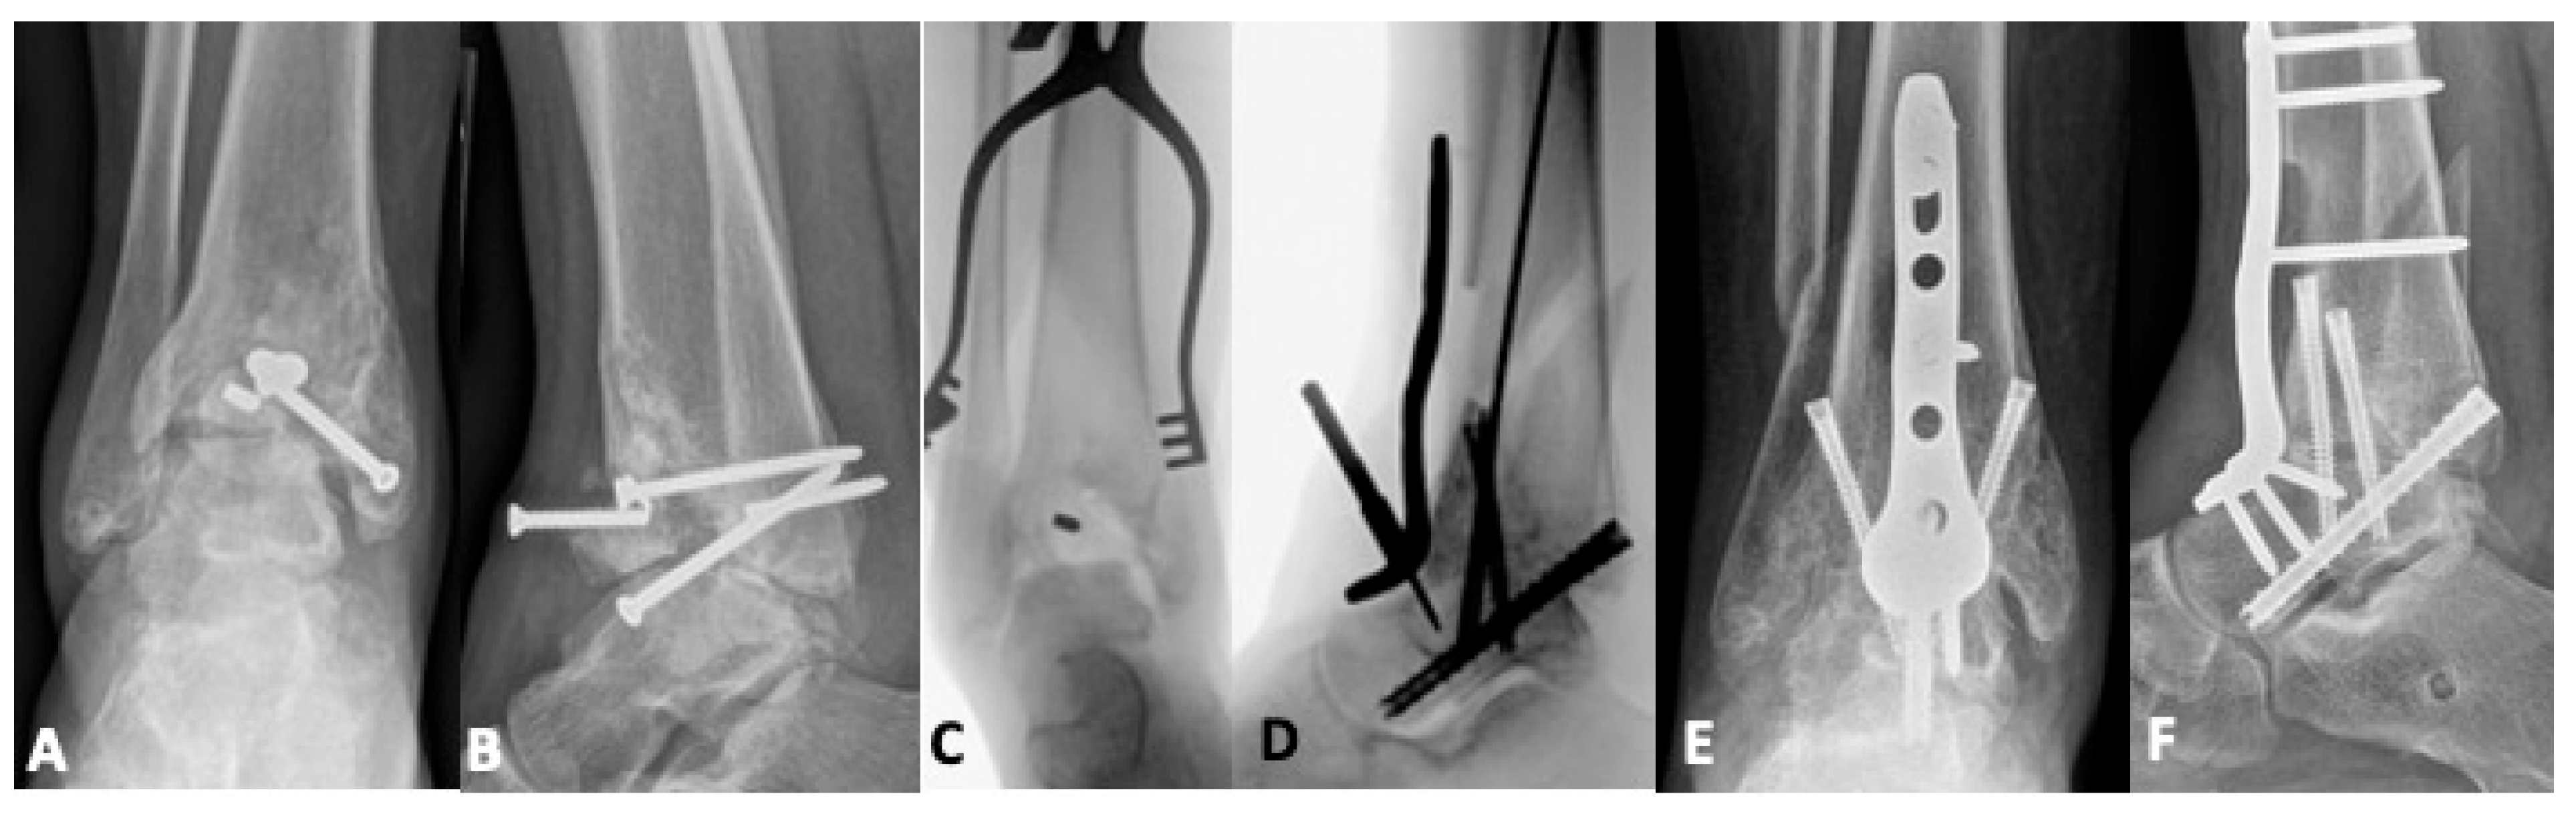

5.1. Revision Operative Fixation

5.2.1. Total Ankle Arthroplasty